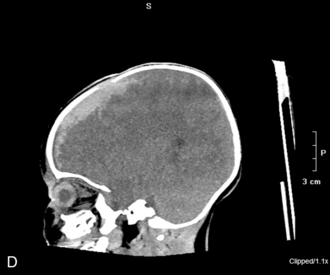

The patient with an SAH may experience a sudden onset of a severe headache (the most common symptom and present in nearly all cases), emesis, syncope, meningismus, and photophobia. These symptoms are associated with a rapid rise in ICP. Left untreated, the child will progress to coma and possibly death. Although spontaneous SAHs can arise from a variety of sources, including aneurysms, coagulation disorders, and small artery ruptures, trauma remains the leading cause of an SAH in children. CT scans performed within 48   hours of a hemorrhage will detect the vast majority of subarachnoid hemorrhages. The blood will appear as a white, hyperdense area in the subarachnoid spaces (see Fig. 11–12, B and C).

Throughout the child's care, the nurse must be alert for signs of increased ICP (see Increased Intracranial Pressure). The sudden appearance of irritability, confusion, lethargy, and pupil dilation must be reported to a physician or other on-call provider immediately. Emergency acute management of sudden increases in ICP requires immediate intervention with support of the airway, oxygenation, and ventilation and administration of mannitol (0.5-1   gm/kg IV) or 3% saline (3-5   mL/kg IV bolus), or both. A CT scan is typically performed to detect any mass lesion requiring surgical intervention; the CT scan also will enable the evaluation of cerebral edema (see Fig. 11-12).20